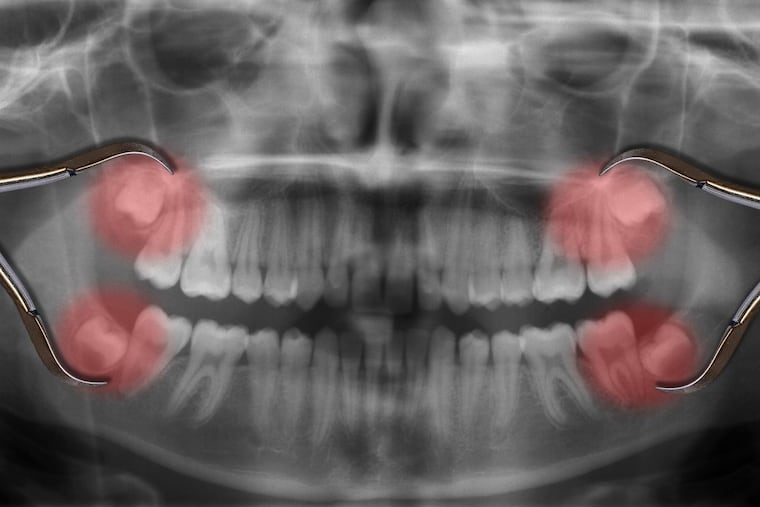

Having wisdom teeth removed has long been associated with at least a temporary loss of the ability to taste, but no one had studied what happened long-term.

Immediately after the procedures, as many as 20% of people lose tasting ability on the side of their tongue adjacent to the wisdom tooth removal, Doty said. Nerves that connect to taste buds at the front of the tongue run near the molar roots and can be damaged during the procedure. The dysfunction usually resolves within a year.